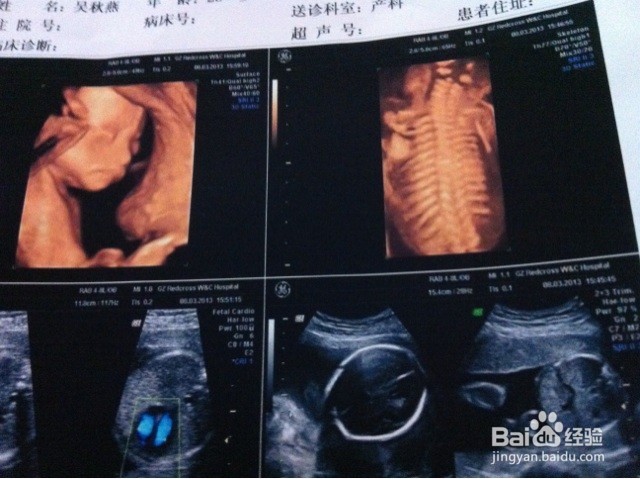

2、第二、系统B超或四维彩超 这个最佳时间是21-24周之间,主要是排除小儿先天性畸形。它主要检查宝宝的生长发育情况,也就是小宝贝的手、脚、心肝脾肺、眼耳口鼻等发育完全没,这个是很有必要的一次检查。